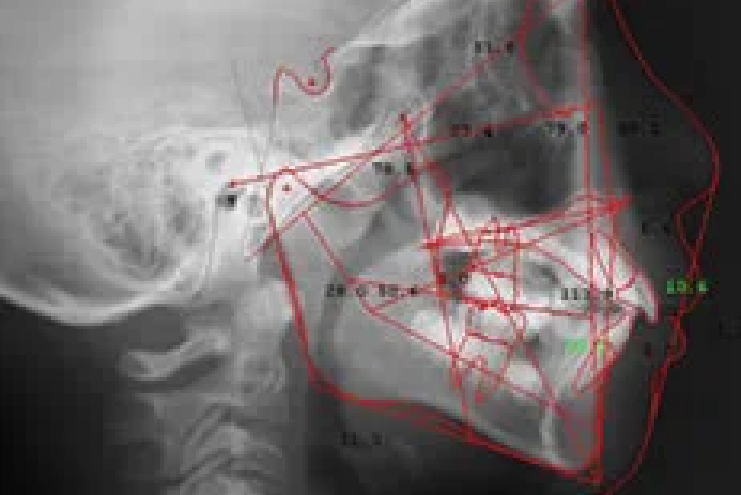

お子様の歯並びやあごの成長状態を正確に把握するために、セファロで分析します。あごや歯の骨格バランス、かみ合わせの詳細を調べることで、将来の歯並びや生え変わりの予測がしやすくなります。